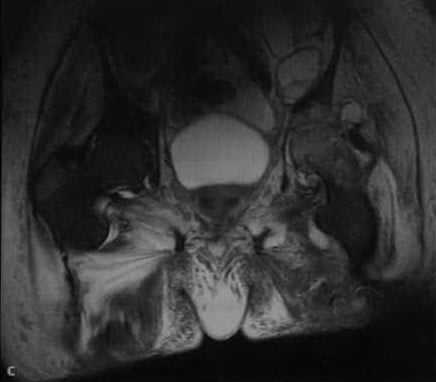

с) МРТ. Последовательность STIR демонстрирует выпот в полости сустава, абсцесс в подвздошно-поясничной области и отек костного мозга в головке бедренной кости и вертлужной впадине.